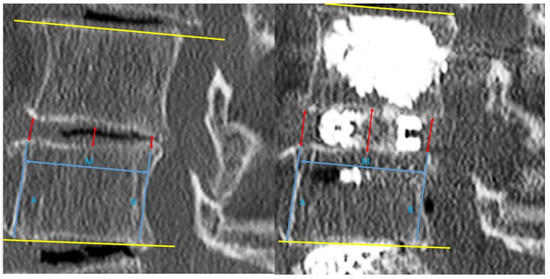

For post-operative evaluation in this cohort of patients, we evaluated clinical outcomes of Visual Analogue Scale at pre-operative, 1 week post-operative, 3 months post-operative and final follow up. Early and late perioperative complications were documented. For radiological evaluation, CT lumbar spine evaluation was done on pre-operative and post-operative day one. We evaluated mid sagittal CT lumbar spine to measure anterior, middle and posterior disc height and focal segmental angle (Figure 3). CT evaluation at mid coronal lumbar spine was done to measure mid coronal disc height and coronal wedge angle (Figure 4).

In terms of radiological results, the position of the implants was satisfactory in all cases. No subsidence of implants was found to have occurred in our cohort at final follow up XR. The means and ranges of pre-operative mid sagittal CT lumbar spine anterior, middle and posterior disc heights were 3.91 (1.71–6.99) mm, 3.8 (0.43–4.98) mm, and 3.84 (0.43–7.03) mm, respectively. The post-operative mid sagittal lumbar spine CT anterior, middle and posterior disc heights were 11.1 (8.18–15.6) mm, 10.2 (7.28–12.4) mm, and 9.12 (5.88–11.5) mm, respectively. The means and ranges of pre-operative and post-operative mid coronal lumbar CT disc height were 3.42 (0.43–4.98) mm, and 10.6 (6.59–14.5) mm, respectively. The pre-operative and post-operative mid coronal lumbar CT wedge angles were 8.02 (0.1°–19.3°) and 5.51 (0°–15.5°), respectively. The pre-operative and post-operative mid sagittal lumbar CT focal segmental angles were 10.9 (−3.4° to 27°) and 12.9 (−1.9° to 31°), respectively.

There was an increase in computer tomographic mid sagittal anterior, middle and posterior disc height of 6.99 (±2.30) mm, 6.28 (±1.43) mm, 5.12 (±1.79) mm, respectively, p < 0.05. Similar findings were shown in CT mid coronal disc height, with an increase of 7.13(±1.90) mm, p < 0.05. There was a significant improvement in CT coronal wedge angle in post-operative scan compared to the pre-operative scan of 2.35 (±4.73°), and in the mid sagittal CT focal segmental angle of 1.98 (±4.69°), p < 0.05.

Figure 4. Left picture was pre-operative and right picture was post-operative mid Coronal Cut of CT Lumbar Spine of L4/5, we measured the pre-operative and post-operative mid Coronal Disc height and Coronal Wedge Angle.